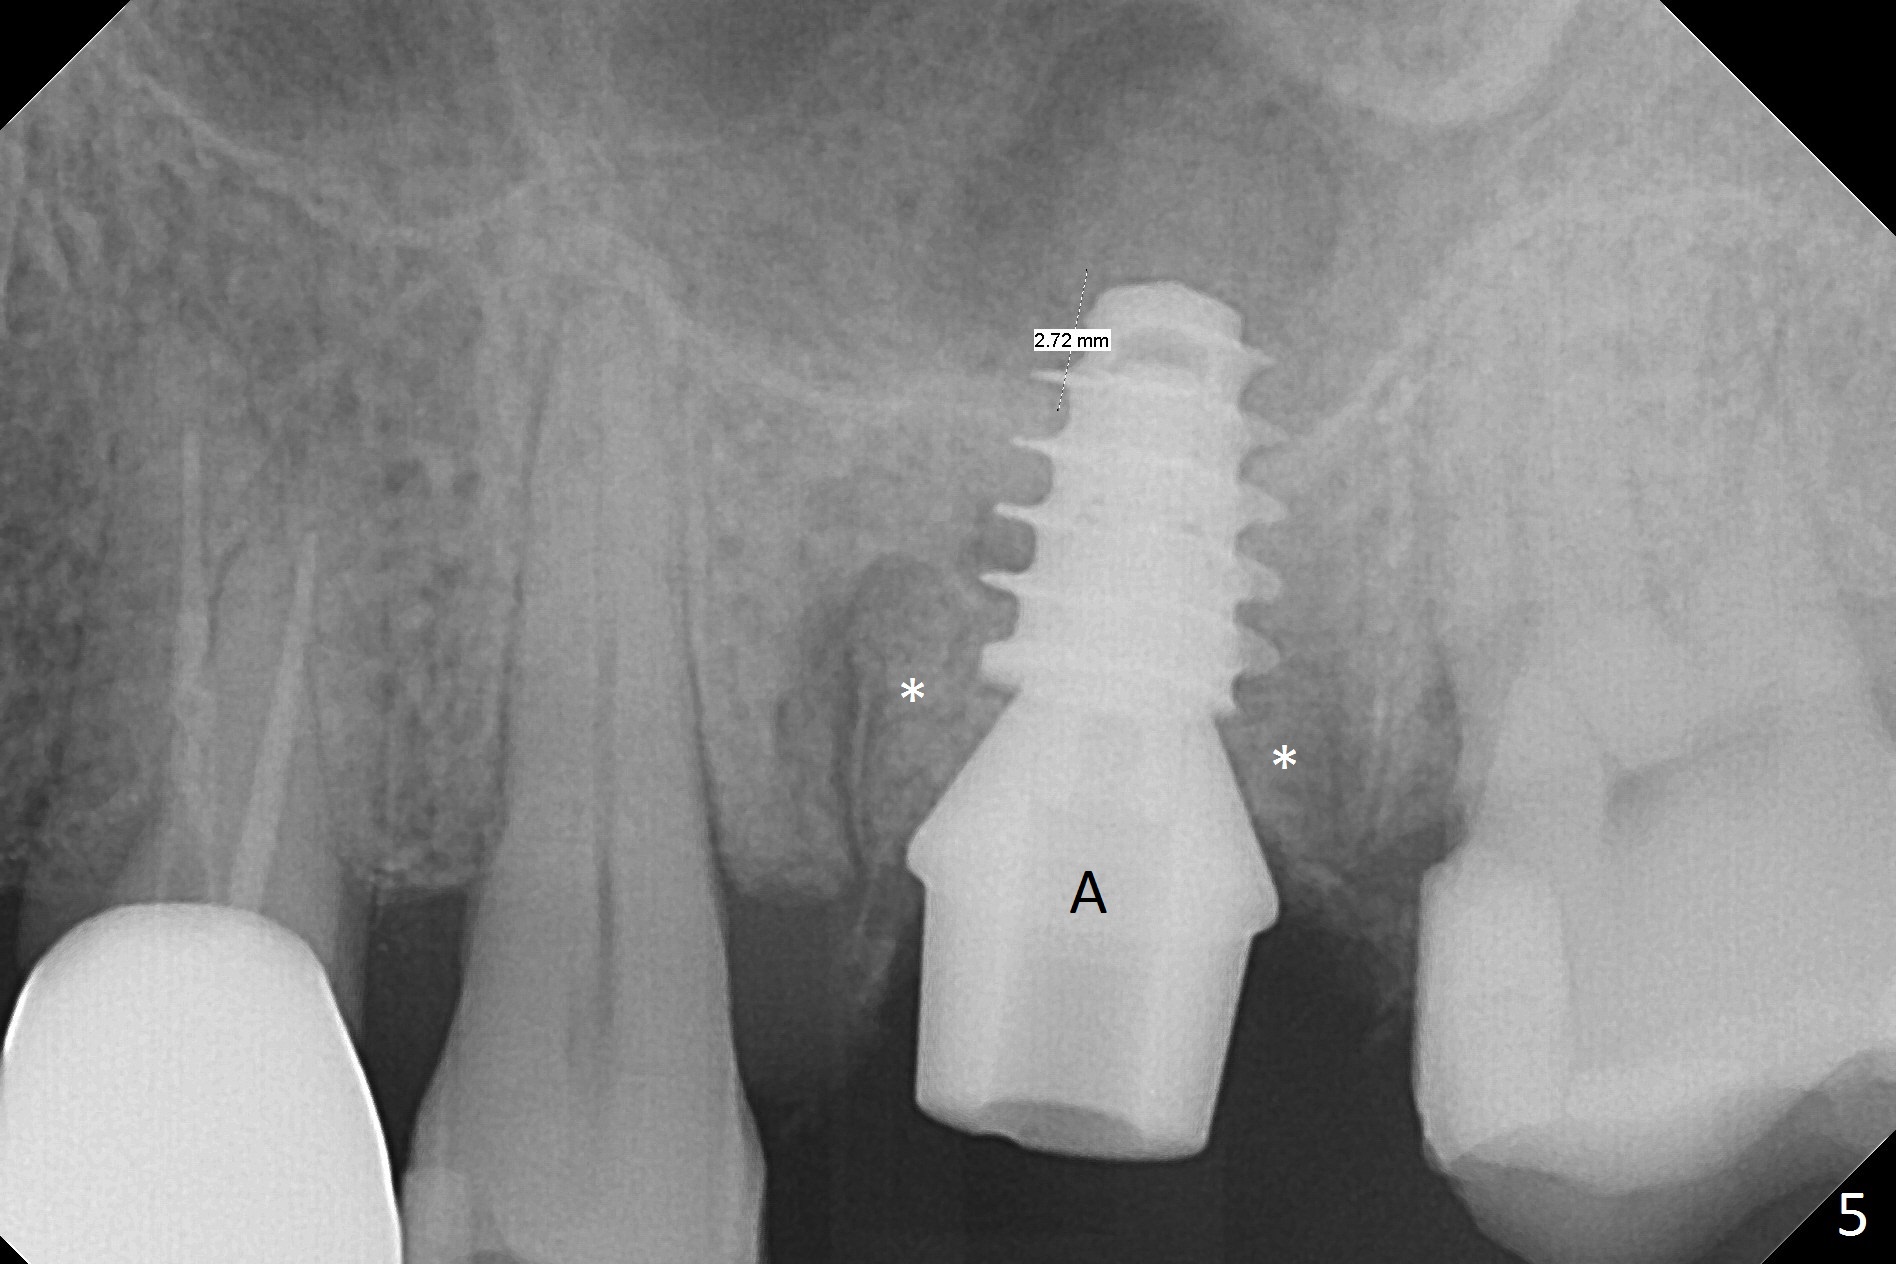

What is unclear preop is the large periapical radiolucency (Fig.1 red dashed line) of the palatal root (P) of the tooth #14. When the tooth is extracted, it is difficult to remove granulation tissue from the palatal apical socket, which is enlarged (Fig.2 (impression of sockets),3). The small dimension of the septum (~4x5 mm (Fig.1 pink) is also unrecognized preop, which leads to sinus perforation when 4.8 mm Magic Drill is used. In spite of use of PRF plug and membrane, allograft does not stay in the osteotomy after placement of 4x11 mm dummy implant or 5 mm tap drill (Fig.4 for 9 mm). Finally a 5.5x7 mm IBS implant is placed with 30 Ncm (Fig.5). After placement of Osteogen plug in the apical portion of the sockets, allograft/Osteogen is placed in the remaining sockets (Fig. 5 *). The latter is partially contained by a 6.5x4(3) mm abutment (A) and ultimately by an immediate provisional.